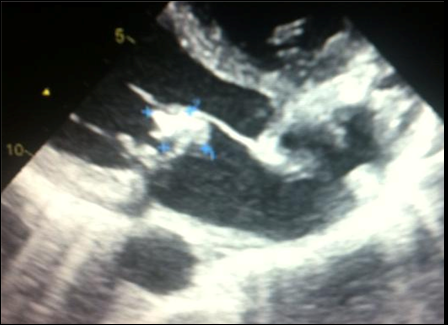

A 48 year old man, farmer originated from South West Tunisia, was first admitted in the nephrology department for acute renal failure in the context of prolonged fever, severe denutrition and loss of appetite. Laboratory exams revealed increased inflammatory biomarkers as well as severe anemia. Renal biopsy showed a non specific interstitial nephritis suggesting an infectious origin. Wright serology returned positive and patient history confirmed consumption of unpasteurized goat milk. Electrocardiogram showed sinus tachycardia and 2D trans thoracic echography 2D (TTE) found a large 25mm mass located in the atrial side of the anterior mitral valve suggesting a vegetation that has resulted in a severe mitral stenosis leading to pulmonary edema (Figure 1) (Figure 2). One day later, the patient developed an ischemic stroke in the right capsulo-lenticular brain area. He received high dose of antibiotics (Vibramycin, Rifampicin and Bactrim) and subsequently underwent a successful urgent surgery with mitral valve replacement number 21. Peroperative examination found a massive infection of the mitral valve with rupture of the anterior valvular chordae (Figure 3). Soon after surgery, renal function returned to normal, general status substantially improved. Antibiotics were maintained for 6 months with an unremarkable course during follow up. After discontinuation of antibiotics, the patient was kept only on oral anti vit K anticoagulant (VKA).

Figure 1 Two-dimensional echocardiography (Left parasternal view) showing large vegetation originated from the anterior mitral valve.

Figure 2 The same vegetation seen on four chamber apical view.